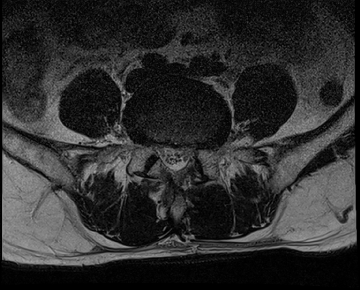

요추 협착증 수술 전·후

2020.08.30

2022.09.06